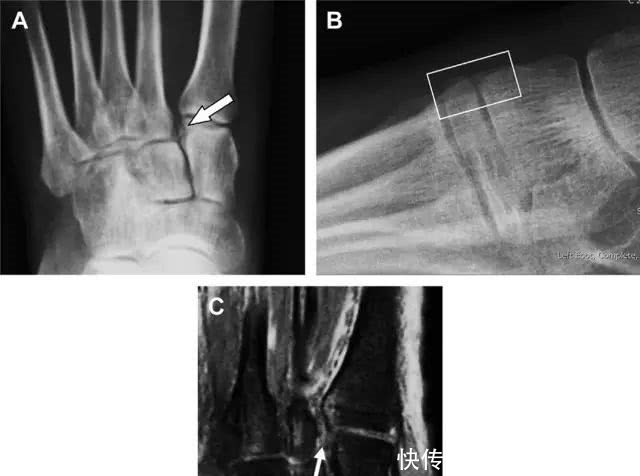

距骨外侧突骨折常因踝外翻背屈时,跟骨上外侧面撞击距骨外侧突下缘导致,或偶尔由踝内翻引起,被称为「滑雪板者骨折」。这种骨折只能在踝关节正位片上发现,而且外踝远端表面软组织肿胀往往是一个重要线索(图 4)。

图 4 距骨外侧突骨折。A 正位片示内翻损伤所致的距骨外侧突撕脱性骨折(箭头);B 另一位患者,踝外翻损伤导致典型的「滑雪板者骨折」,X 片上可见一较大的三角形骨折块(方框);C 第二位患者的 MRI 矢状位 T1 加权像示横行骨折(箭头)